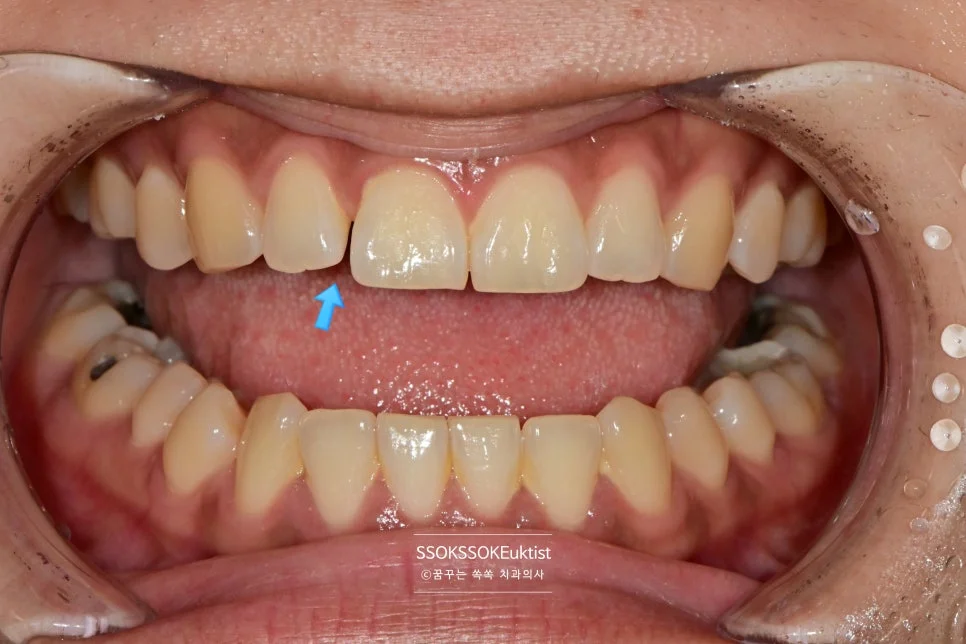

측면에서 바라본 사진입니다. 생각보다 틈이 커서 한 치아만 치료할 경우 한 개 치아만 너무 커 보이는 게 될 것 같아, 양쪽 치아 모두 레진으로 치료하는 것이 좋습니다.

레진 치료는 어떻게 하면 될까요? 그저 예쁘게 치료하면 됩니다^^ 복잡한 치료 내용들은 굳이 아실 필요 없습니다^^

예쁘게 잘 치료된 것 같으신가요? 그럼 그냥 OK입니다!

그리고 안쪽에 닿는 점을 조정하여 치아가 벌어지는 경향을 최소화해주면 치료는 종결됩니다.